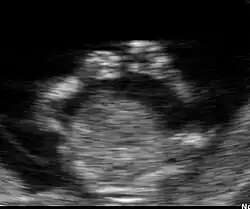

Figure 7. La distinction des organes intra-abdominaux est possible à 12 semaines

Sur la figure 7 on distingue à gauche une zone intra-abdominale blanche correspondant à l'intestin du fœtus. Dans cette zone blanche, une petite tache noire qui est la vessie. Enfin, à droite des intestins, on peut distinguer le foie et les poumons.

Les 2 bras d'un fœtus à 12 semaines

La face est explorable. Les deux orbites sont distinguables ainsi que les deux cristallins. Les membres se distinguent nettement. Le diagnostic d'anomalie des membres est possible à ce stade.

Les malformations graves du cerveau sont détectables comme l'anencéphalie ou l'holoprosencéphalie. Les malformations cardiaques ne sont pas détectables en routine à ce terme.